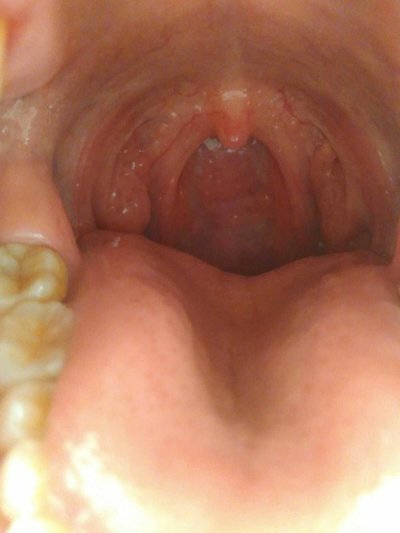

Esophageal cancer is a common digestive tract cancer in humans. It is the eighth place in the world, and the incidence rate of cancer is sixth. In China, it ranks the fourth in the death order of urban cancer and the third in rural areas. What reason is esophagus cancer caused? Next, I'd like to share my views with you.

The third reason: fungi and nitrosamines factors, eating moldy food can cause cancer, has been a consensus, such as grains, pickles and moldy food in Aspergillus flavus, has a strong carcinogenic effect. Dietary factors, drinking, bad eating habits, and chronic food stimulation can cause the damage of esophageal mucosal barrier, leading to the occurrence of precancerous lesions, and ultimately the formation of esophageal cancer.